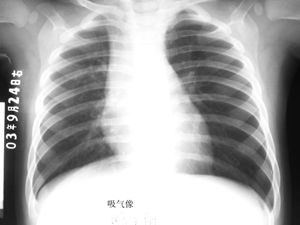

以下是引用听蝉观竹在2007-3-11 18:44:00的发言:[br]左侧支气管异物。[br][br]吸气时,由于异物活瓣式,双侧肺通气几乎相等,所以双肺透亮度一样,纵隔居中;呼气时,健侧呼气通畅,肺缩小,而患侧呼气受阻,肺部气体明显较健侧多,所以透亮度明显增强,呼气受阻非压力较健侧增高,所以纵隔向健侧移位,如果在透视下可以看到纵隔摆动。[br]